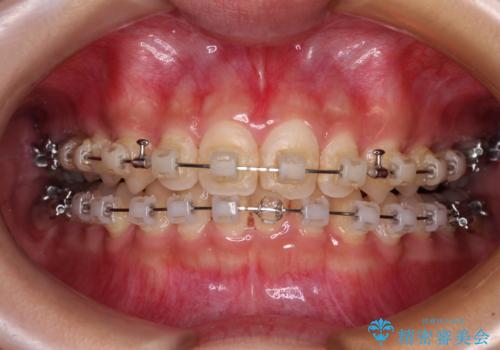

- 矯正装置

- クリアブラケット

- 治療期間

- 2年1ヶ月

下顎の装置が頻繁に脱落し、治療は難航しましたが、当初予定の2年間で無事に治療を終えることができました。